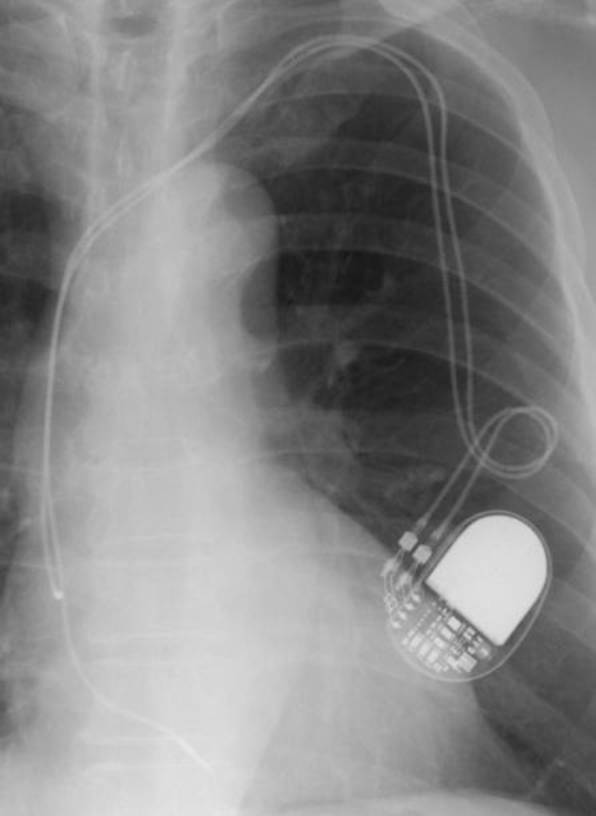

1.病名、症状:人工ペースメーカー感染

2.手術名とその内容:手術日2012/01/24 ペースメーカー除去、体外ペーシング、新規再移植時(ペースメーカー植込み術)、鎖骨の下に4-5cmの皮膚を切開し、5cm程度のポケットを作成します。その中に、心臓内に挿入したリード線1~2本と電池(ジェネレータ)を植え込みます。

新規のPMは、メーカーを変える。MRI(magnetic resonance imaging=磁気共鳴映像法)対応でドイツ製とのこと(国内では駄目)。サイズは従来のものより大きいというので、皮膚に負担が掛かると、感染の原因となるのではと。感染しないことが、大切ですからと、先生。

第5回目となる手術は、リード(2本)の除去、ジェネレーター(PM)の除去、入院前に腫脹した箇所の切除となる。

PMはどうやら取り出せた。次にリードであるが、スクリューイン(先端がキルクをあける時のツール状)されている。S先生が1,2,3,・・・と数えながらそれぞれを回し始める。モニターでは分解性能のせいか、抜け切れたのか、不明のようだ。其の時の痛みは全く無い。リードの抜けた部分を切る。静脈に挿入する手前の各リードにストッパー状のもの(リードを固定するためにかしめる物で其の上を糸で縛る)が取り付けてあるようだ。これを見つけないと残余のリードを取り出せない。困難に打ち当たる。剣ヶ峰だ。

駈け付けた別の先生が、“これは(あと)1時間以上かかるぞ”と。どうやら少し離れた場所の椅子に座り、引き継いだ先生と外科のT先生の問いに指示を出している。辛うじて1本は見つかった。が、もう一本に窮している。もっと先かな、と切り開き抉る。ウッ、痛い、う~ん。T先生、手前じゃないかと少し戻って切除。あった! 2本ともスムーズに引き出せた。2008年05月20日以来3年8ヵ月か。

2012012402PM

ペースメーカーは、BIOTRONIK社製、エヴィア(Evia DR-T電池寿命14年)に替わった。ホームモニターリングをし、ドイツにあるセンターへPMのロギングデータを夜中に毎日送る。MRIにも耐えるということだが、日本では承認されていない。

2012020201PM(植込み中のため、体外式ペーシング利リードもある)

2012021001PM

2012020202PM

2012020203PM